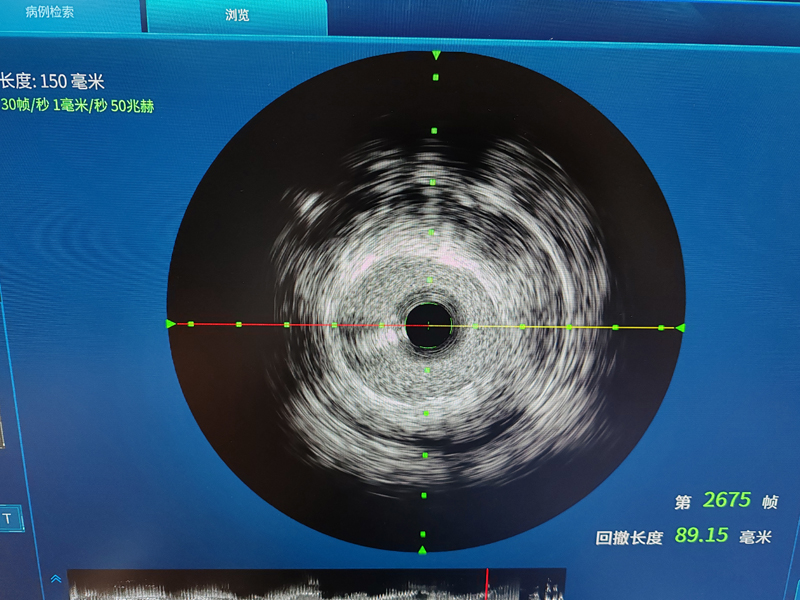

设备精良:配备有DSA、IVUS、多功能心电监护仪、心电机、除颤仪、高压注射器、临时起搏器、多导电生理仪、射频仪、主动脉内球囊反搏仪、呼吸机、运动平板工作站、BNP和TnI快速检测仪、血气分析仪、心脏彩超机、体外反搏仪、心肺运动功能测定仪、ABI指数测试仪等国内外先进设备。

IVUs引导下冠脉精准介入治疗

心血管内科作为衡阳市医学会内科专业委员会主委单位及心血管内科专业委员会主委单位,2019年获批衡阳市心力衰竭防治重点实验室建设项目,2021年获批湖南省动脉硬化性疾病临床医学研究中心,2022年获批湖南省省级临床重点专科,目前结合心血管六大中心,四个病区,在IVUS引导下的冠脉精准个治疗、ECMO+IABP辅助循环支持下危重症患者的冠脉介入治疗、心脏瓣膜病TAVAR治疗、恶性心律失常的三维标测治疗、心血管疾病的危重症患者康复治疗等方面做到省内领先!